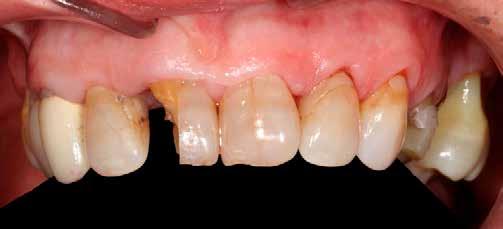

A korai harmicas éveiben járó hölgy rendelőnkbe érkezésének oka a jobb felső nagymetsző fog bizonytalan érzkenysége, elmondása alapján gyermekkorában trauma érte a felső frontrégiót. A frakturált klinikai koronákat kompozittöméssel helyreállították, egyéb kezelést akkor nem tartottak szükségesnek. Az utóbbi hónapokban tapasztalt érzékenység miatt kereste fel rendelőnket. A klinikai vizsgálat (1. és 2. kép) és a CBCT felvétel (3. kép) alapján diagnosztizált külső gyökérreszorpció megoldására a fog eltávolítását, implantátum

behelyezését, majd csavarozott rögzítésű, cirkónium-dioxid vázas, kerámialeplezésű korona készítését terveztük [1., 5., 6., 8.].